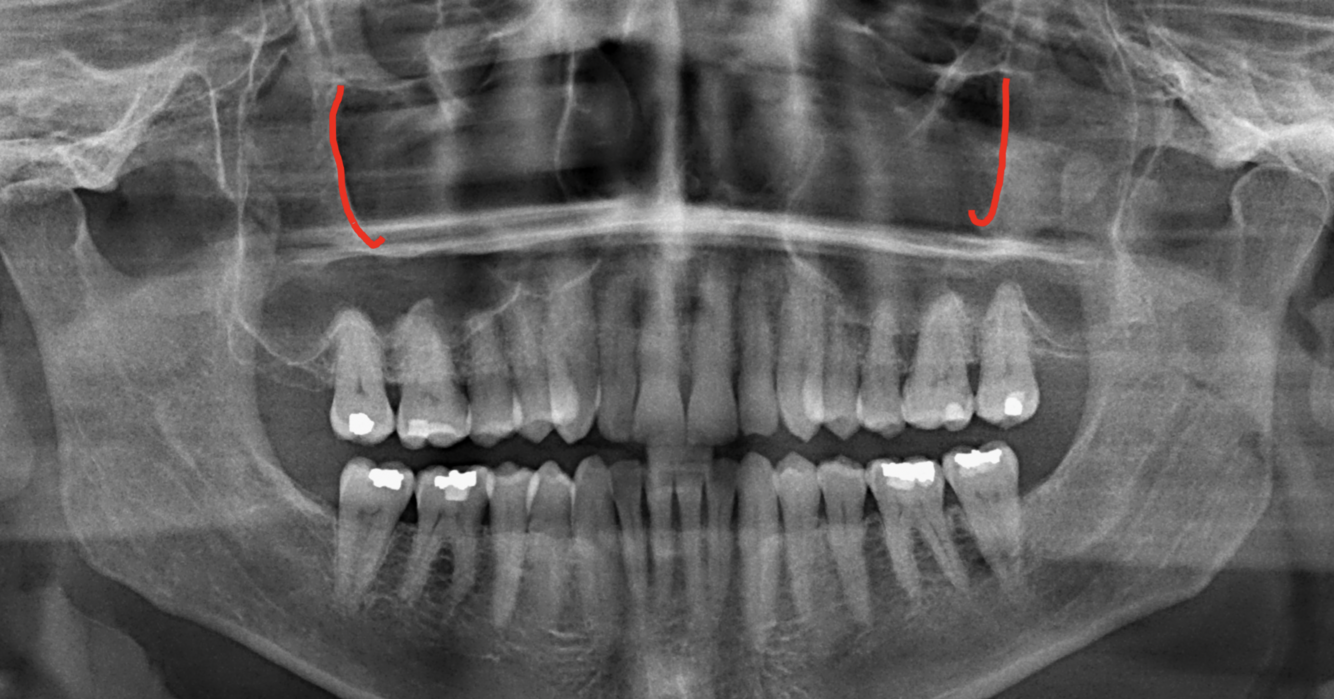

What does the red indicate in the following image?

Coronoid process